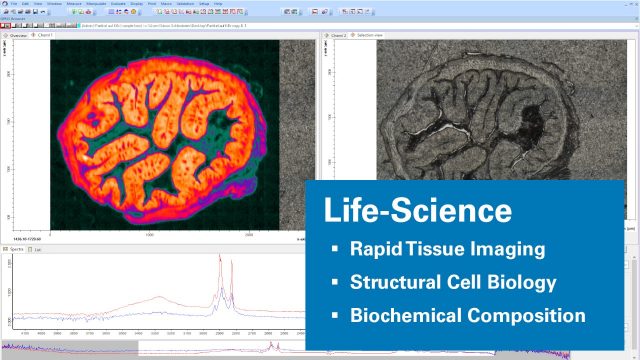

Life Science

Analysis with micro-FT-IR provides important insights into biology. It enables the discovery of specific disease patterns, dysfunctional tissue or even new disease related biomarkers. With fast imaging capabilities and a huge field of view the LUMOS II simplifies lengthy tissue investigations.